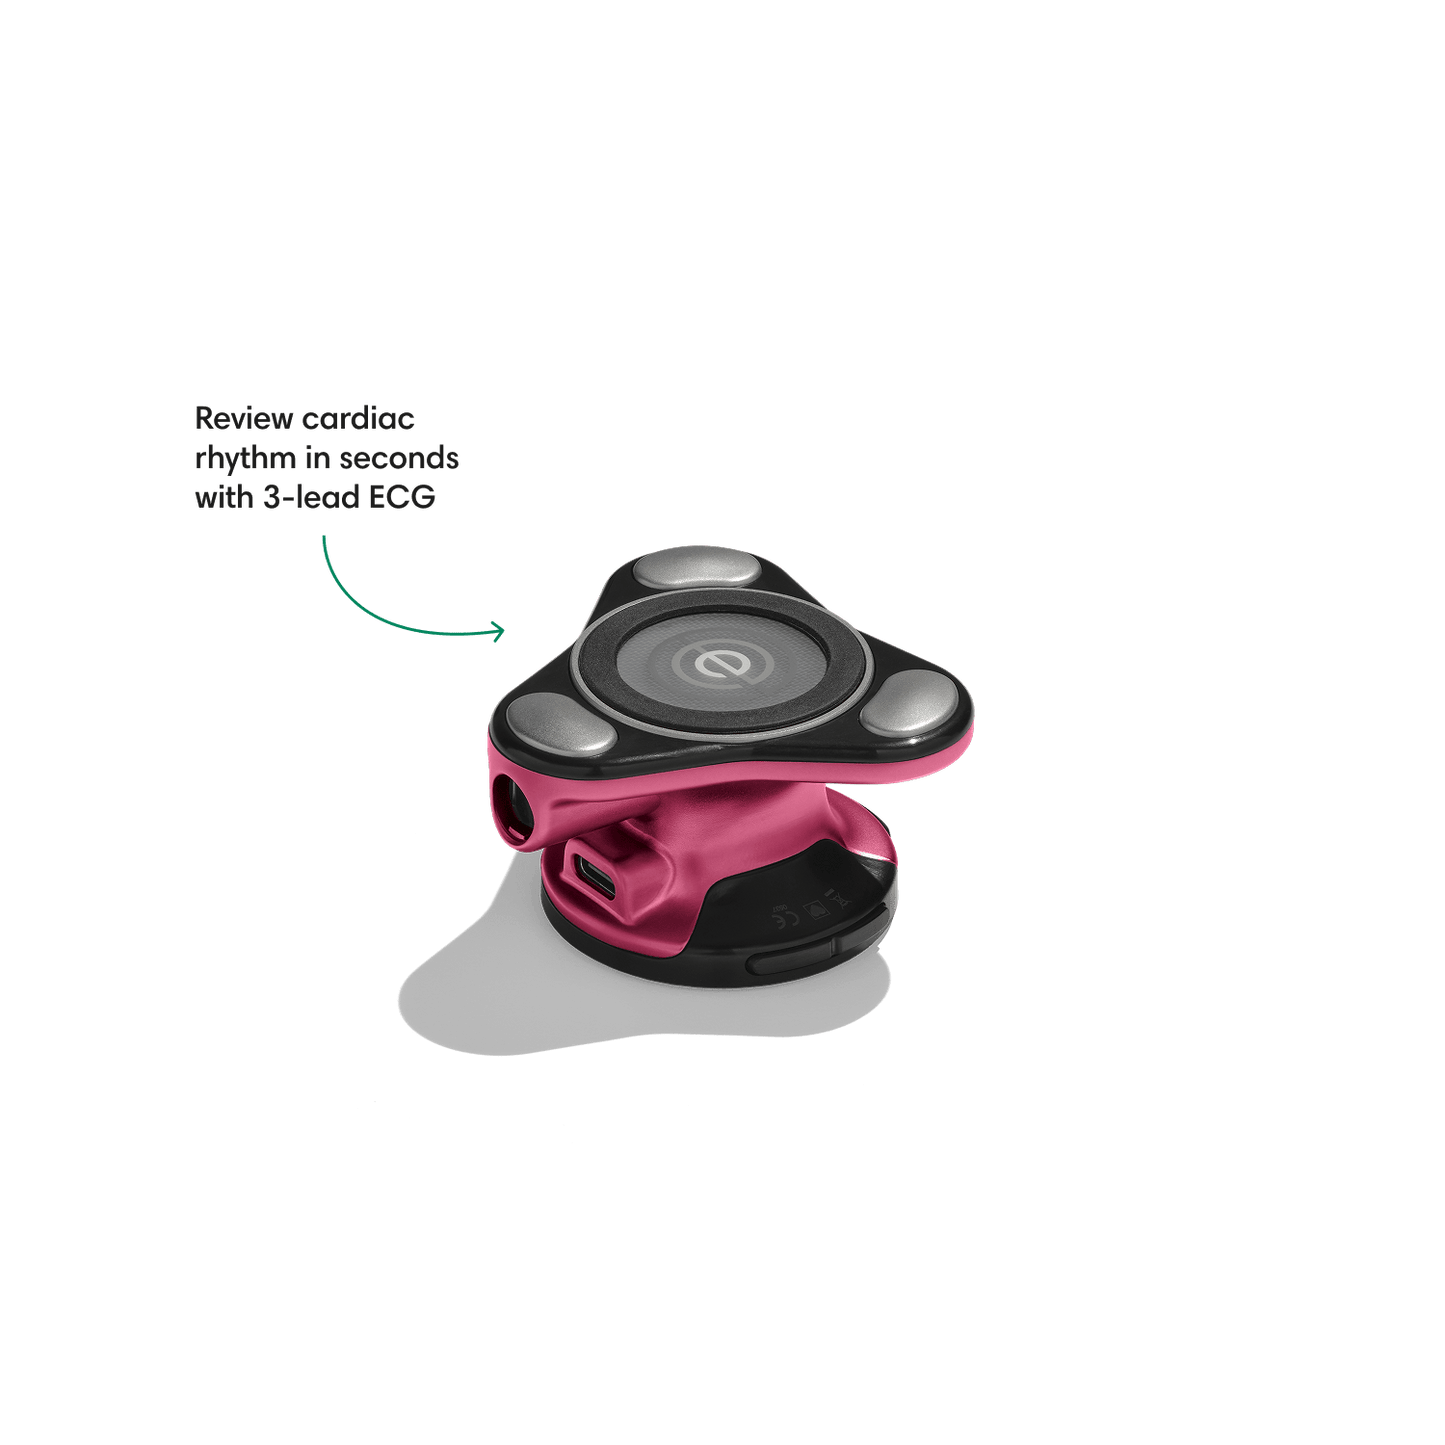

Go beyond sound alone.

For the first time ever, measure heart rate, visualize 3-lead ECG, and see detection results — right on a built-in, full-color display.